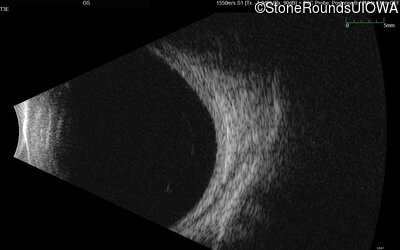

AR Stargardt Disease (IIA)

Age at visit:

62 years

OD

OS

Light Perception sc

AR Stargardt Disease

ABCA4

Gln636Stop CAG>TAG

His1406 del1caC

AR